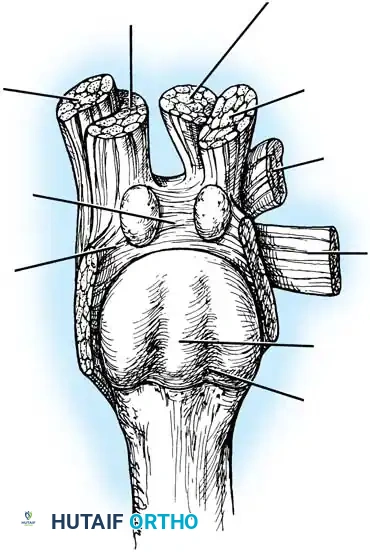

Hallux valgus (lateral deviation of the great toe) is not a single disorder, as the name implies, but a complex deformity of the fi rst ray that frequently is accompanied by deformity and symptoms in the lesser toes (Fig. 78-1). Often the angle between the fi rst and second metatarsals is more than the 8 to 9 degrees usually considered to be the upper limits of normal. The valgus angle of the fi rst metatarsophalangeal joint also is more than the 15 to 20 degrees considered to be the upper limits of normal (Fig. 78-2). If the valgus angle of the fi rst metatarsophalangeal joint exceeds 30 to 35 degrees, pronation of the great toe usually results. With this abnormal rotation, the abductor hallucis, which is normally plantar to the fl exion-extension axis of the fi rst metatarsophalangeal joint, moves further plantarward (Fig. 78-3). In this case, the only restraining medial structure is the medial capsular ligament with its capsulosesamoid portion (inserting into the base of the proximal phalanx) (Fig. 78-4) and capsulophalangeal portion (inserting into the plantar plate). The adductor hallucis, which is unopposed by the abductor hallucis, pulls the great toe further into valgus, stretching the medial capsular ligament (particularly the capsulosesamoid), attenuating this structure, and allowing the metatarsal head to drift medially from the sesamoids. In addition, the fl exor hallucis brevis, fl exor hallucis longus, adductor hallucis, and extensor hallucis longus increase the valgus moment at the metatarsophalangeal joint, further deforming the fi rst ray. The deep transverse intermetatarsal ligament runs between the plantar plates at the metatarsophalangeal joints and does not insert into bone on the adjacent sides of the metatarsal heads. Finally, the sesamoid ridge on the plantar surface of the fi rst metatarsal head (the crista) fl attens because of pressure (abutment) from the tibial sesamoid (Fig. 78-5). With this restraint lost, the fi bular sesamoid displaces partially or completely into the fi rst intermetatarsal space (see Fig. 78-2). In this situation, the patient is bearing less weight on the fi rst ray and more on the lesser metatarsal heads, increasing the likelihood of transfer metatarsalgia, callosities, and stress fracture of a lesser metatarsal.

Fig. 78-5 A, Plantar surface of fi rst metatarsal head. Entire sesamoid sling with attached intrinsic musculature has been rotated distally off metatarsal head to present schematically relationships of muscle, tendon, capsule, ligaments, and articular confi guration of fi rst metatarsophalangeal joint. B, As metatarsal head moves medially, sesamoid sling apparatus becomes valgus deforming force, and metatarsal rotates (pronates) on its longitudinal axis. Intrinsic and extrinsic muscle balance is lost, and deformity increases. ( A after Beverly Kessler; courtesy of LTI Medica and The Upjohn Company.)